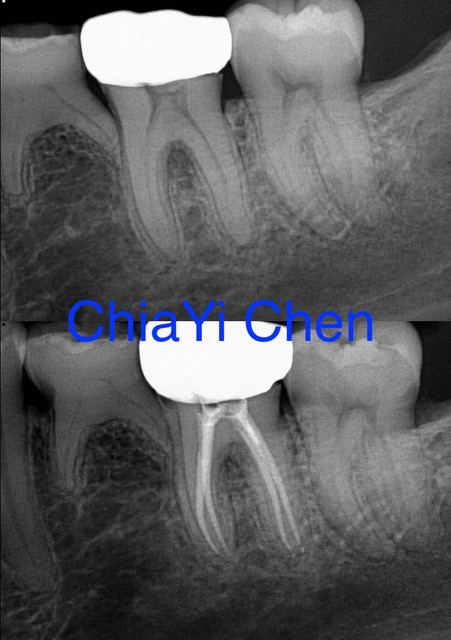

The Procedure of a Root Canal Treatment

To begin, our endodontist will start by numbing the area around the affected tooth using local anesthesia. This ensures that you feel little to no pain during the procedure. Once you are numb and comfortable, our endodontist will create a small access hole in the crown of your tooth. Through this access point, they will carefully remove any infected or damaged pulp from within the roots and chambers of your tooth. This helps eliminate any infection and prevents further damage to surrounding tissues.

After cleaning out all traces of infection, our endodontist will then shape and sterilize the canals before filling them with a rubber-like material called gutta-percha. This material provides stability and prevents reinfection.